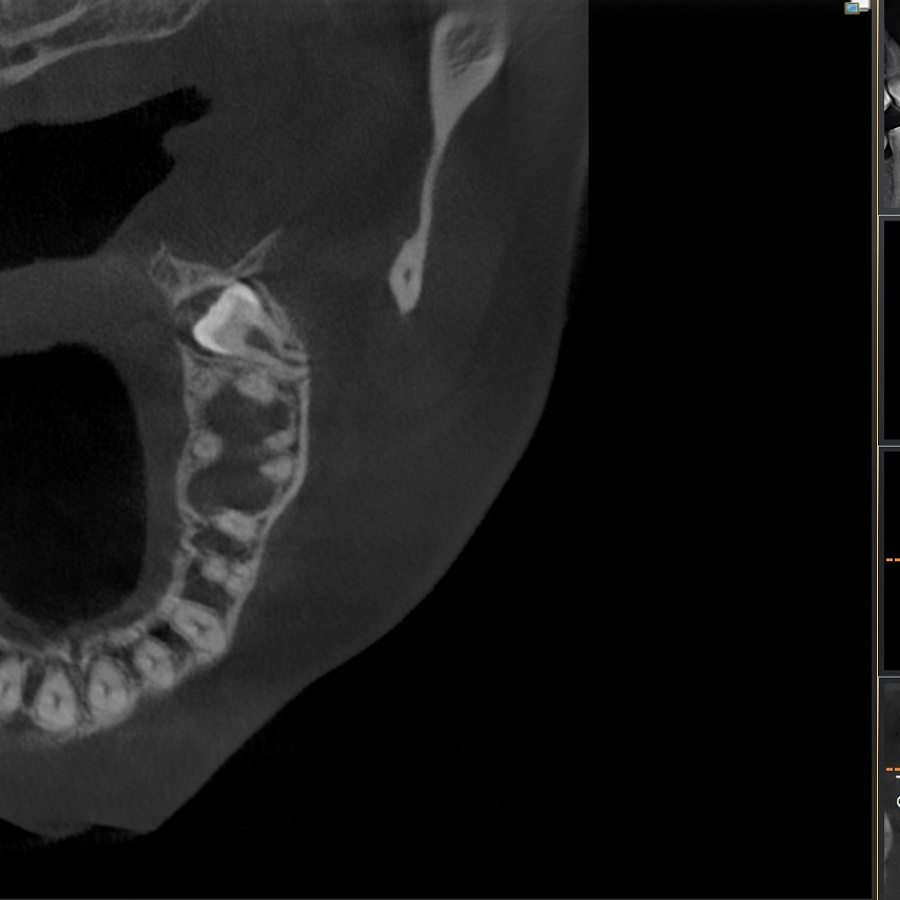

Зуб не прорезался, лежит горизонтально и направлен в сторону твёрдого нёба, мешает проведению ортодонтического лечения, выпрямлению зубных рядов. Около зуба проходит несколько важных анатомических структур, которые нельзя задеть, плюс зуб полностью погружён в костную ткань.